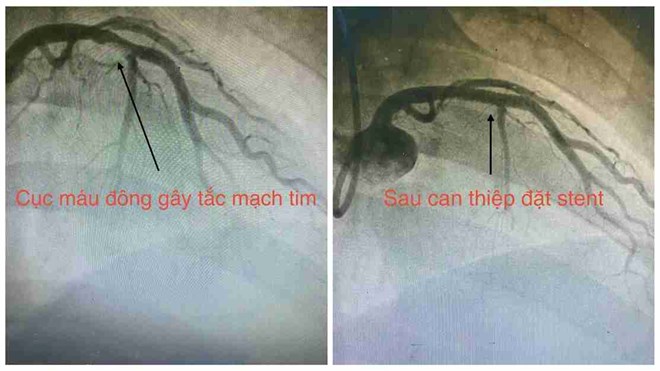

Sau khi nhập viện, bệnh nhân được chẩn đoán nhồi máu cơ tim cấp và nhanh chóng chuyển đến phòng can thiệp tim mạch.

Các bác sĩ đã tiến hành đặt stent kịp thời để tái thông mạch vành. Sau can thiệp, tình trạng người bệnh ổn định và tiếp tục được theo dõi, điều trị tại khoa Tim mạch can thiệp.